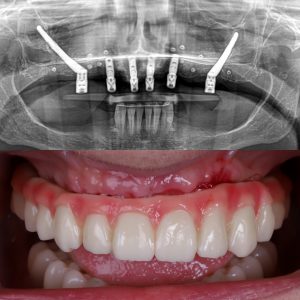

En esta foto se puede observar uno de los tipos de implantes sin tornillos más usados, la estructura para arcada completa

Los implantes dentales sin tornillos son implantes subperiósticos o yuxtaóseos: una estructura de titanio hecha a medida que se adapta al contorno del hueso maxilar o mandibular. A diferencia de los implantes tradicionales, aquí no se introduce un tornillo dentro del hueso; la estructura se apoya sobre él y se fija bajo la encía.

- Se diseña una base metálica personalizada a partir de un TAC 3D.

- Esa base se apoya sobre el hueso, por debajo del periostio.

- De la estructura salen unos pilares que emergen a la boca.

- Sobre esos pilares se colocan los dientes fijos.